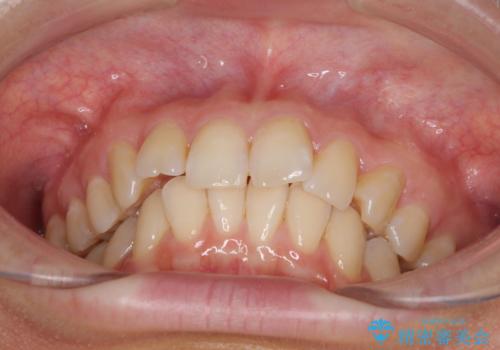

- 前歯の叢生と口元の閉じにくさを気にして来院された患者様です。

奥歯の咬み合わせを見ると、上顎が下顎に対して相対的に前方にありました。